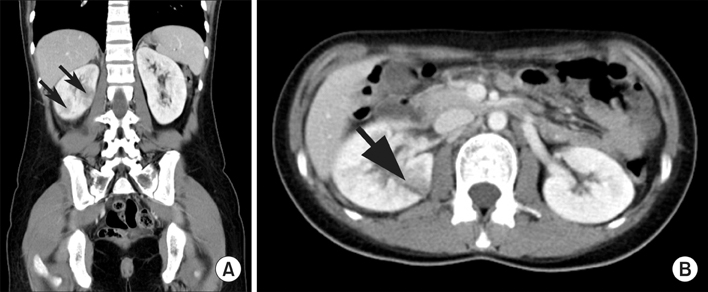

영상 검사(CT): 치료에 호전이 없거나 폐쇄가 의심되는 경우 등에서 시행

합병증: 패혈증, 신농양, 기종성 신우신염 등